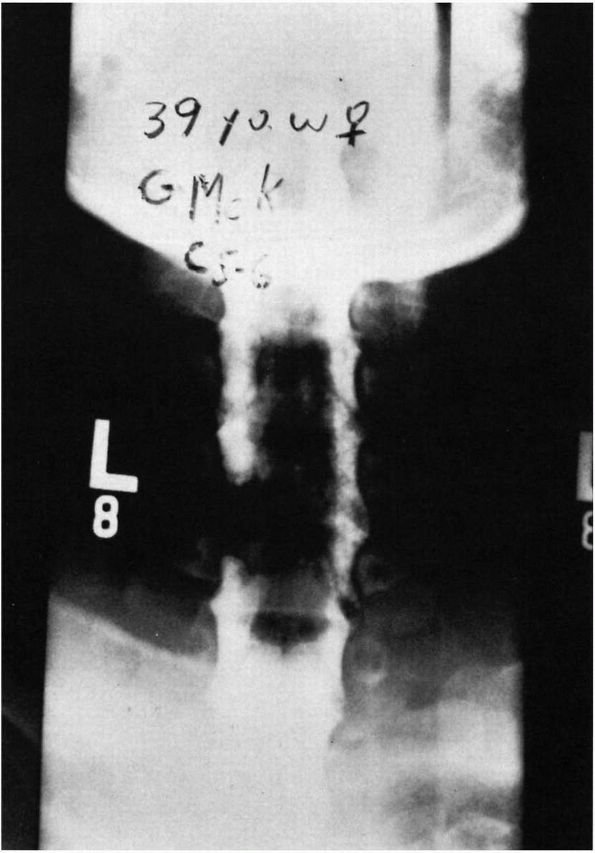

FIGURE 11-3.

Acute torticollis due to neuritis of the spinal accessory nerve. The severely painful spasms were unilateral, temporary, and relieved by infiltration of the nerve with a local anesthetic. In contrast, spasmodic torticollis is bilateral, persistent or intermittent, and unaffected by injection of the nerve. |